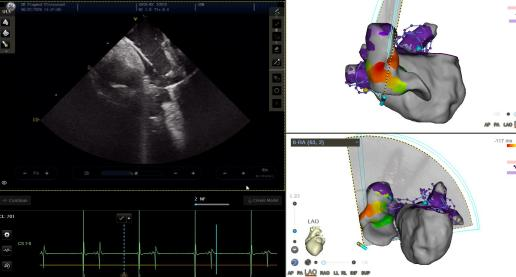

在下午的手术演示中,学员通过导管室观摩与手术画面实时转播,学习了零射线三维脉冲消融手术流程。通过张曦教授、匡晓晖教授的手术演示与细致讲解,突出了中心零射线三维脉冲消融手术流程的要点及特点:

房间隔穿刺位点选择:超声结合三维直视下穿刺位点尽量偏低微偏前,帮助导管更好到位肺静脉。

VIZIGO可调弯鞘的应用:可视可调弯鞘提供实时三维指引,判断导管操作位置及辅助贴靠。

ICE结合TPI贴靠双重验证:心腔内超声直视确认导管贴靠形态,结合TPI贴靠指示双重验证贴靠效果。

三维评判损伤形成区域:FAM coloring实时消融损伤显示,Grid overlap indication同步显示TPI阳性grid点。